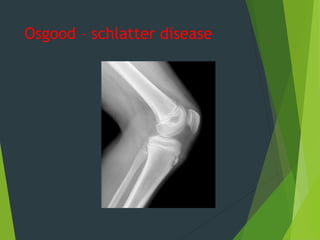

Osgood – schlatter disease

Osgood schlutter`s disease: It is osteochondritis of upper tibial tubercle ,affecting children 8-15 years old . The tibial tuberosity become swallown , tender and extension of the knee joint against resistant is painful . X-ray : show irregular fragmentation of apophysis in which infra patellar tendon is inserted . Treatment : spontaneous recovery is usually occur and it is necessary to modified child activity e.g., stop plying foot ball and stop cycling . If pain persist then put in plaster cylinder for about 1-2 months occasionally excision of the fragmented piece by operation is done